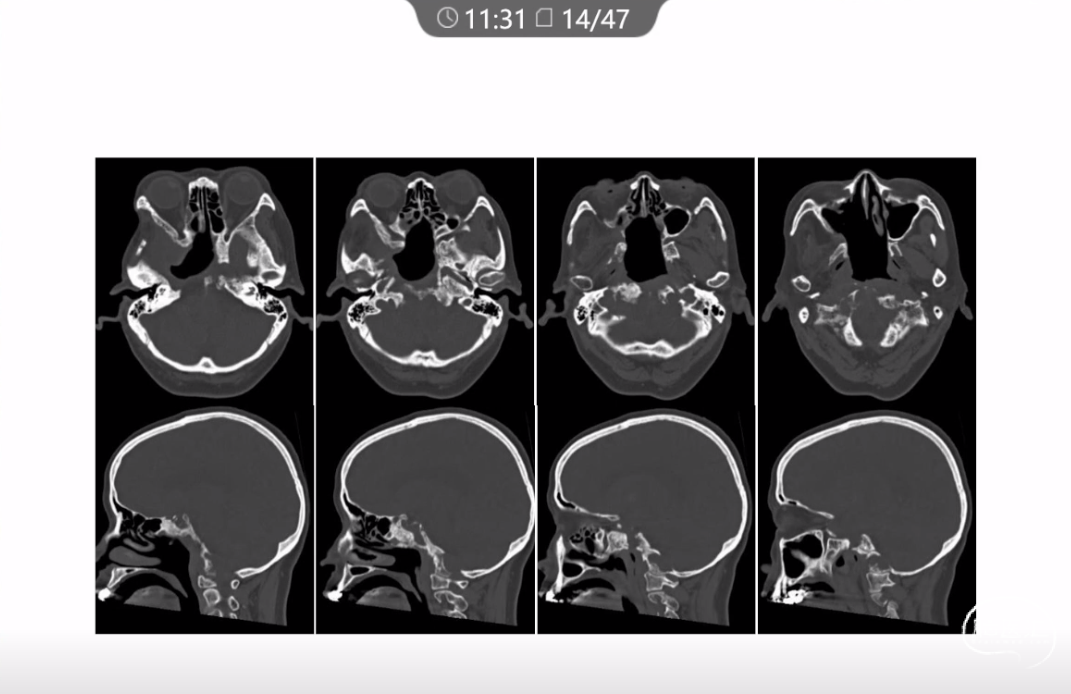

本文主要内容为:脊索瘤临床特点、治疗选择,以及多个手术病例。